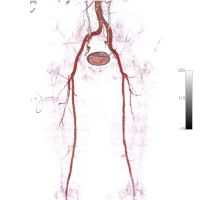

Pastki ekstremal tomirlar tomografiyasida CT angiografiyasi tufayli qonning holatini batafsil o'rganish, tomirning har qanday qismini diqqat bilan tekshirib ko'rish va qon oqimining buzilishini aniqlash mumkin.

Pastki ekstremal MKHT anjiyografi arterial yotqiziqning yuqori tezlikli multislitsli hisoblangan tomografiyasi bo'lib, kontrast idishlarni qo'llaydi. Ko'pincha quyidagi muammolarni aniqlash uchun beriladi:

Ushbu tashxis usuli yordamida mutaxassis ko'p kanalli arterial kanalning 3 o'lchamli tasvirlarini oladi. Bu usul eng ilg'or va informatsion hisoblanadi.